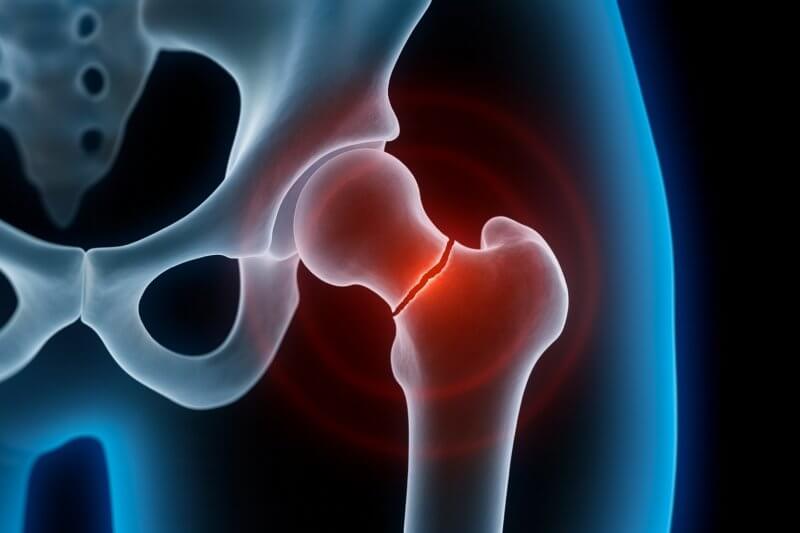

W którym miejscu dochodzi do złamania szyjki kości udowej?

Staw biodrowy jest stawem kulistym utworzonym przez panewkę kości miednicznej (acetabulum) i głowę kości udowej (caput femoris). Otoczony jest torebką stawową, a stabilizowany przez silne więzadła. Szyjka kości udowej, będąca miejscem złamania, łączy głowę kości udowej z trzonem i znajduje się w obrębie torebki stawowej – stąd nazywana jest strukturą wewnątrztorebkową. Jej ukrwienie pochodzi z naczyń okalających udo, co czyni ten obszar szczególnie podatnym na niedokrwienie w przypadku urazu. Złamanie szyjki kości udowej zaburza dopływ krwi do głowy kości udowej, prowadząc do martwicy jałowej (osteonecrosis). Ze względu na anatomiczne położenie i ograniczone ukrwienie, złamania w tym miejscu są trudne do leczenia i wymagają interwencji chirurgicznej.